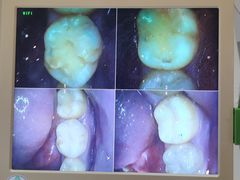

• 泰禾口腔医院

• -泰禾口腔医院

匿名用户 | 23-02-16